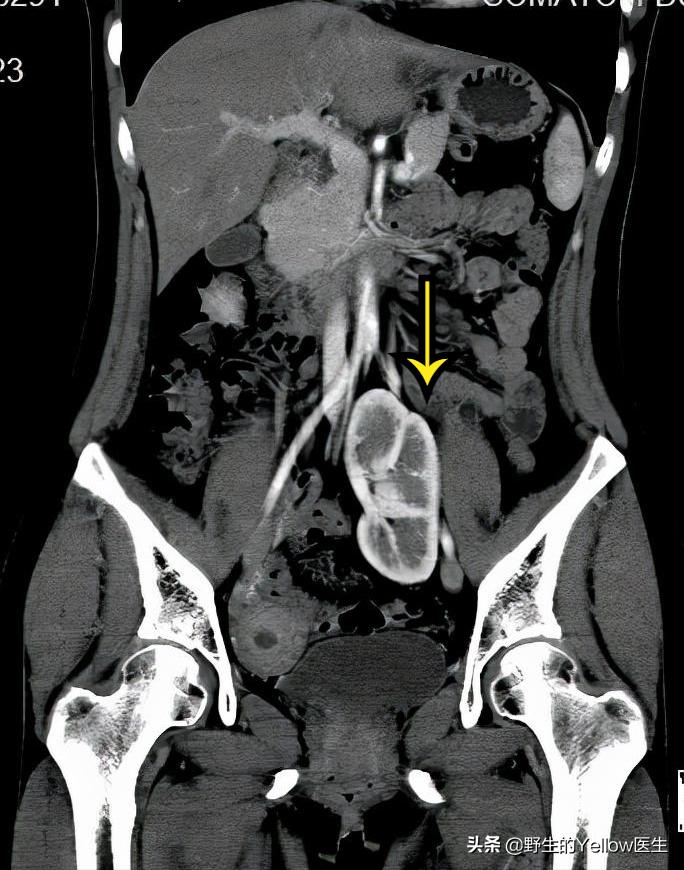

CT发现还不仅于此。这个病人的左肾也不在生理位置,异位在盆腔。

正常的肾脏大概在腰部。

这个病人恰好子宫跟肾脏在分化的过程中发生了点小问题,导致了右侧单角子宫跟左侧异位肾。然后左侧的卵巢没有子宫帮忙固定,就在盆腔游离。结果她左侧腹股沟管比较薄弱,卵巢就掉进左侧腹股沟管,形成左侧腹股沟卵巢疝。